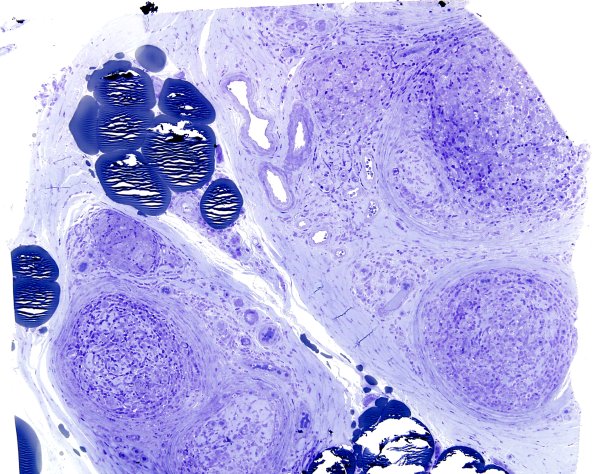

Case 6 No History ---- 6A1 Low magnification image of the nerve biopsy specimen with well developed granulomas. (Plastic section)